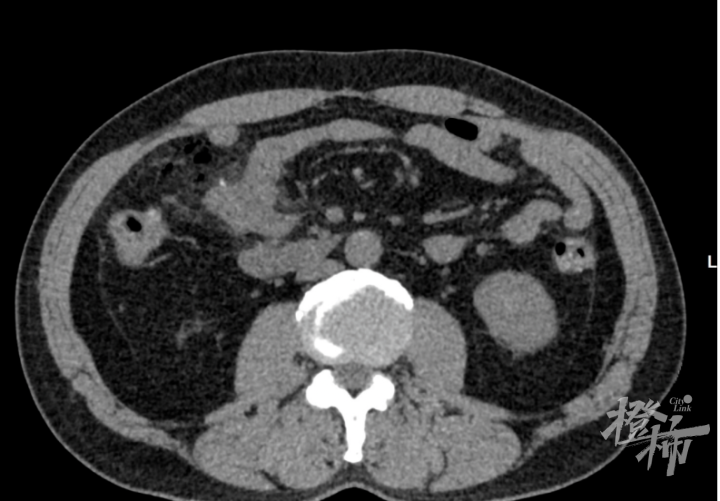

陈大伯的CT检查图像(医院供图)

然而,经验丰富的医生们并没有放弃,他们进一步观察CT图像,终于发现了线索:陈大伯右中腹部肠管内出现了一处致密影,周围肠系膜间隙还有游离积气,这些征象与肠穿孔高度吻合。考虑到肠管内的致密影可能是手术改变或其他异物,医生们进一步询问了陈大伯前一晚的饮食情况。